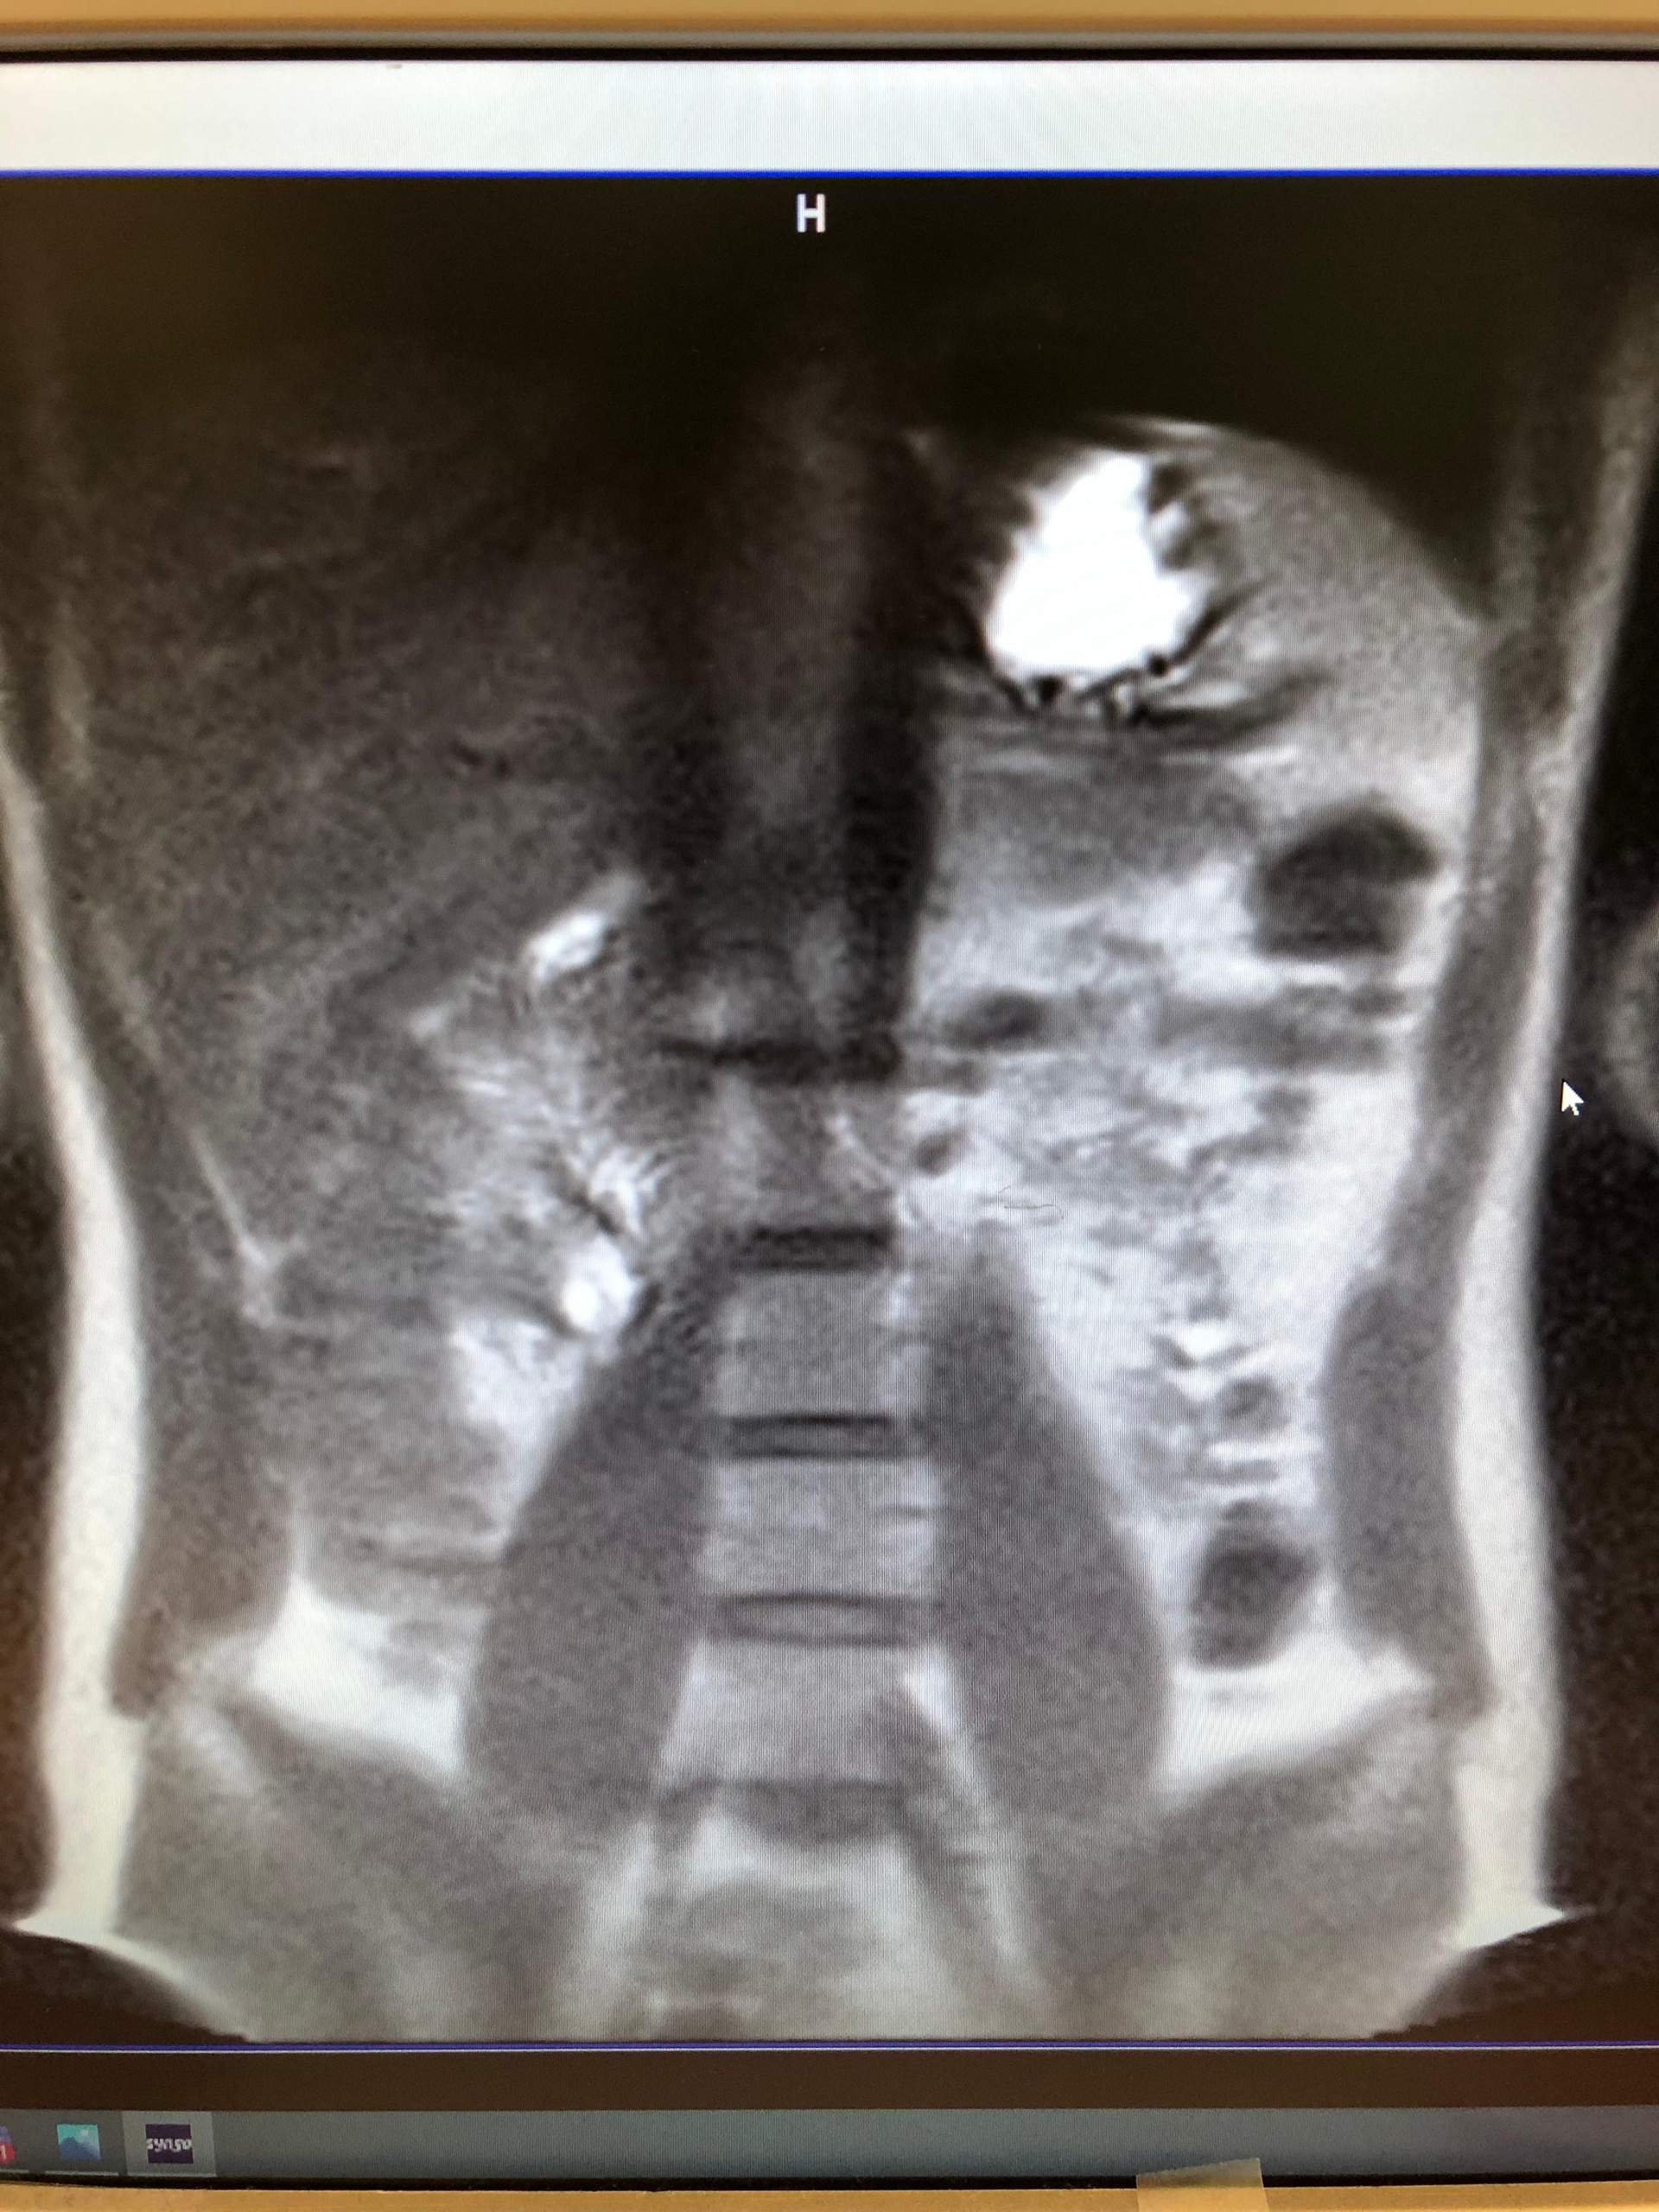

Hirntumoren KI erkennt, welche Therapie wirkt • . Während schon die Termini vielfältig sind, gestaltet sich die Differentialdiagnose noch umfangreicher Was bedeuten weiße Stellen im CT? Bei dem weißen Punkt rechts im Bild neben der Halswirbelsäule handelt es sich um eine Markierung auf der Haut, die den Schmerzpunkt anzeigt.